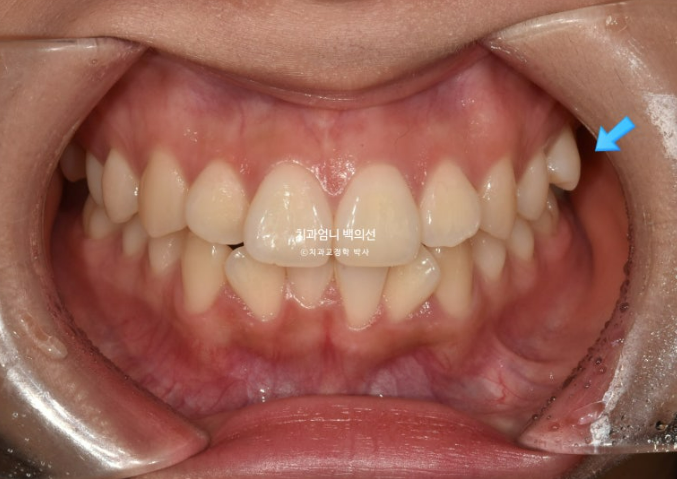

2023년 12월 앞니 부분교정을 원해서 내원한 분 입니다.

앞니 두 개가 크기도 하고 내려와 있습니다.

파란 화살표에 작은어금니 덧니도 보입니다.

아래 앞니가 많이 삐뚤 합니다.

어금니 교합이 그리 좋은 편은 아니었지만 환자분은 씹는데 불편함을 못 느끼는 상태였고 앞니 배열만 원하셨습니다.